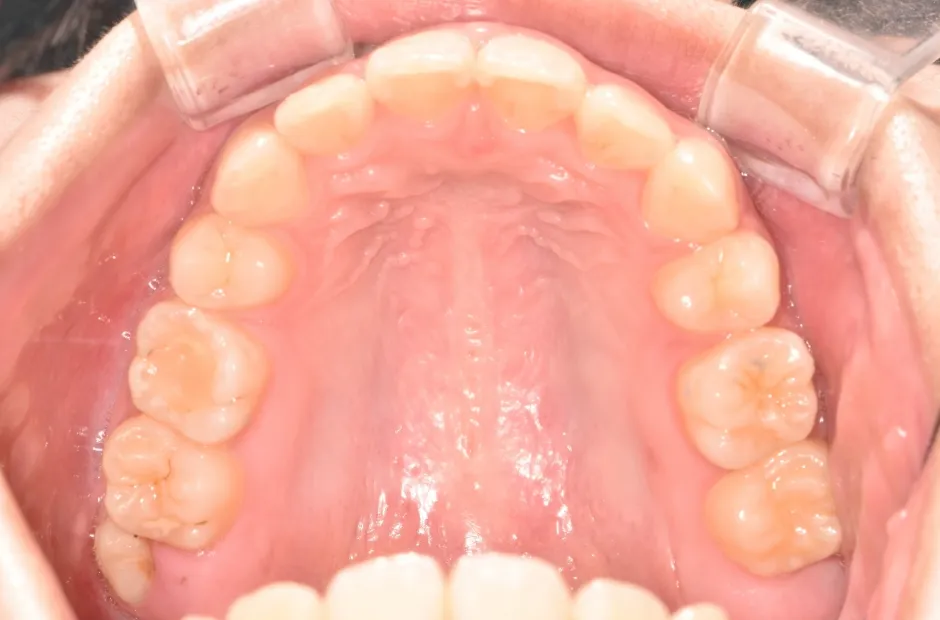

叢生

| 診断名・主訴 | 叢生 |

|---|---|

| 年齢・性別 | 43歳・女性 |

| 治療期間・回数 | 2年7か月 27回 |

| 治療に用いた主な装置 | 舌側矯正 |

| 抜歯部位 | 両顎4,4 |

| 治療費 | 100万円(税抜) |

| リスク・副作用 | 装置による違和感・疼痛・歯肉退縮・歯根吸収・虫歯のリスクなど |